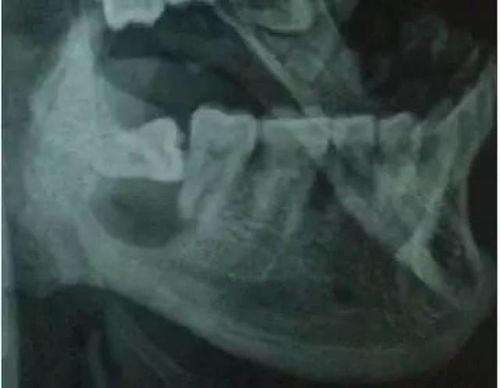

别急,让我带你一探究竟。在拔智齿的视频中,你可以看到医生们是如何使用专业的工具,小心翼翼地分离智齿与牙槽骨的连接。他们会用牙挺、牙钳等工具,将智齿从牙槽骨中拔出。整个过程看似简单,但实际上需要医生们丰富的经验和精湛的技艺。